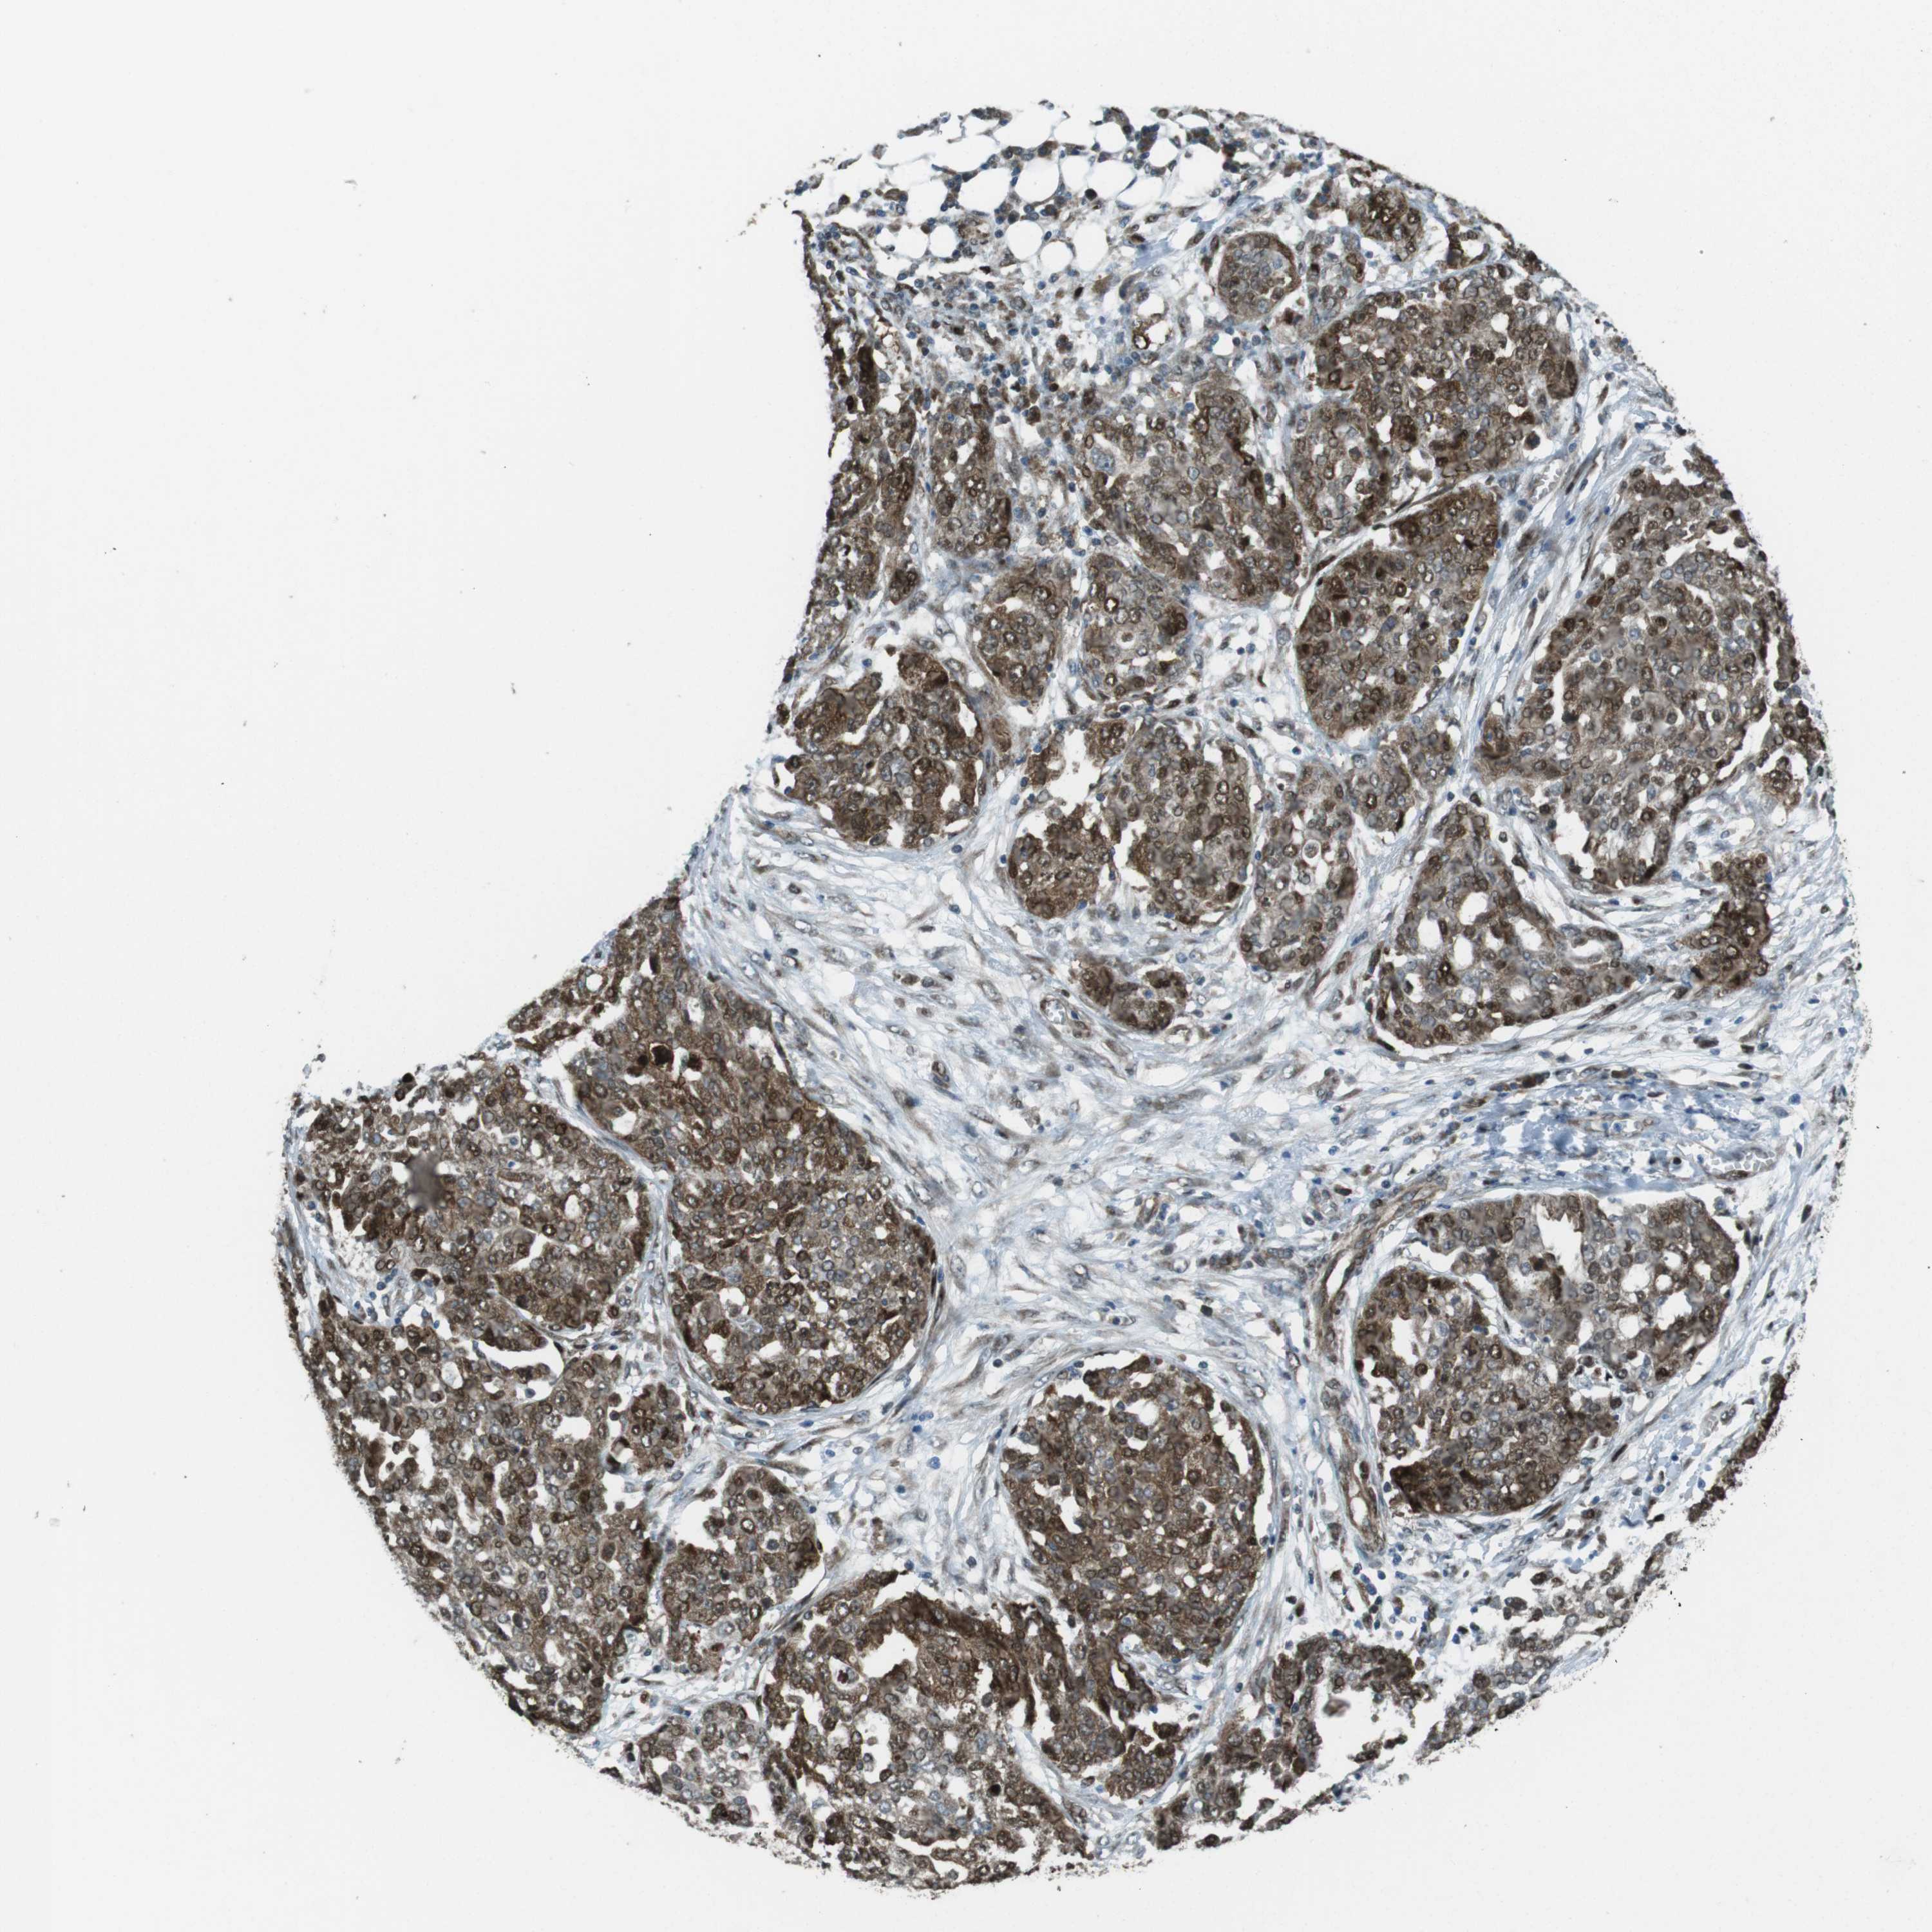

OVARIAN CANCER - Protein expressioni

A mouse-over function shows sample information and annotation data. Click on an image to view it in a full screen mode. Samples can be filtered based on level of antibody staining by selecting one or several of the following categories: high, medium, low and not detected. The assay and annotation is described here.

Note that samples used for immunohistochemistry by the Human Protein Atlas do not correspond to samples in the TCGA dataset.

Antibody stainingi

Antibody staining in the annotated cell types in the current human tissue is reported as not detected, low, medium, or high, based on conventional immunohistochemistry profiling in selected tissues. This score is based on the combination of the staining intensity and fraction of stained cells.

Each image is clickable and will lead to virtual microscopy that enables deeper exploration of all samples and also displays staining intensity scores, fraction scores and subcellular localization as well as patient and tissue information for each sample.

Antibody HPA015705

Staining

High

Medium

Low

Not detected

Intensity

Strong

Moderate

Weak

Negative

Quantity

>75%

75%-25%

<25%

None

Location

Nuclear

Cytoplasmic/membranous

Cytoplasmic/membranous,nuclear

Cystadenocarcinoma, serous, NOS

Carcinoma, endometroid

Cystadenocarcinoma, mucinous, NOS

Carcinoma, NOS